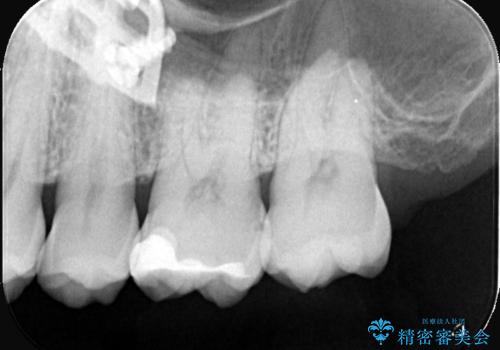

初診でいらした患者様で、口腔内を確認したところ左上6番目と7番目の歯の接する面を中心に両方の歯に虫歯が認められたため、セラミックインレーでの修復治療となりました。

左上6番の歯には元々修復物が入っていましたが、それも一度除去し新たにMOD窩洞のセラミックインレーをセットしました。

左上7番咬合面裂溝の着色部分は今後エアフロー等を使用し落としていく予定です。